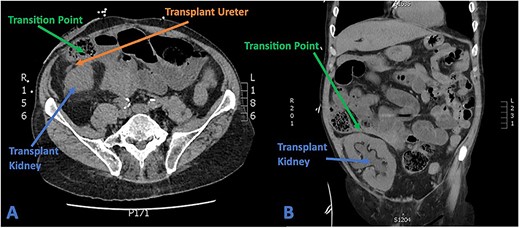

His full blood count and biochemistry showed a significant leucocytosis with a WCC of 36.2 × 109/l, serum lactate of 6.6 mmol/l, and severe decline in renal function as demonstrated by acute rise of serum creatinine to 285 umol/l (baseline 103 umol/l). A subsequent CT scan showed substantial hydronephrosis and hydroureter of the transplanted kidney with distended small bowel loops established in close proximity to the ureteric-ileal conduit anastomosis with an identifiable transition point (Fig. 4). Initial conservative management included copious fluid resuscitation, intravenous antibiotics, and bowel decompression via nasogastric tube. A decision, however, was made for urgent operation when repeated review showed new tachycardia, hypotension, worsening pain with increased analgesic requirements, and generalized peritonism.

(A) Axial CT section showing transplant ureter coursing anterior to kidney transversing over the transition point of SBO. (B) Coronal CT section showing faecalized small bowel approaching transition point with gross hydroureter and hydronephrosis of transplant kidney.